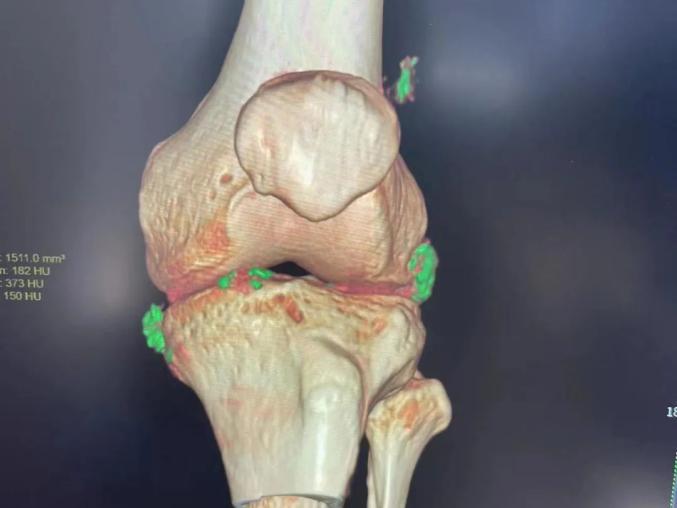

“关节痛只是冰山一角!”她指着陆先生的关节能谱CT图像叹息:绿色代表尿酸盐晶体,像刀一样扎在关节滑膜上,引起强烈的红肿和热痛;更可怕的是,这些“隐形杀手”会悄悄附着在肾脏上,导致肾结石、肾衰竭甚至心脑血管疾病。

膝部骨能谱CT显示绿色尿酸盐晶体(帮助诊断痛风性关节炎)